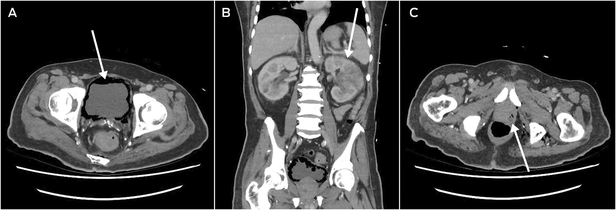

He returned to hospital six weeks after discharge from the Australian hospital, after being found unresponsive at home, with a preceding two‐week history of lethargy, fatigue, and anorexia. He was in septic shock with a temperature of 39°C, tachycardia, tachypnoea, and a Glasgow Coma Scale score of 10. CT scan revealed severe emphysematous cystitis (Box 2, A), left‐sided pyelonephritis (Box 2, B), prostatic abscess (Box 2, C), and gas within the lower pelvis. Operative source control with complete urinary exenteration was deemed not survivable. He was admitted to the intensive care unit, catheterised, and treated with IV meropenem, vancomycin and clindamycin. The infectious diseases team reviewed him within 24 hours of his admission, identifying his epidemiological risk factors for hypervirulent K. pneumoniae. Urine and blood cultures grew K. pneumoniae noted to have a hypermucoviscous phenotype (positive string test), following which his antibiotic regimen was rationalised to high dose IV ceftriaxone monotherapy. After initial clinical improvements, his condition deteriorated with new fevers, worsening confusion, and rising inflammatory markers and lactate on his blood tests, and IV metronidazole and ciprofloxacin were added. He gradually improved, receiving a further six weeks of oral ciprofloxacin monotherapy.